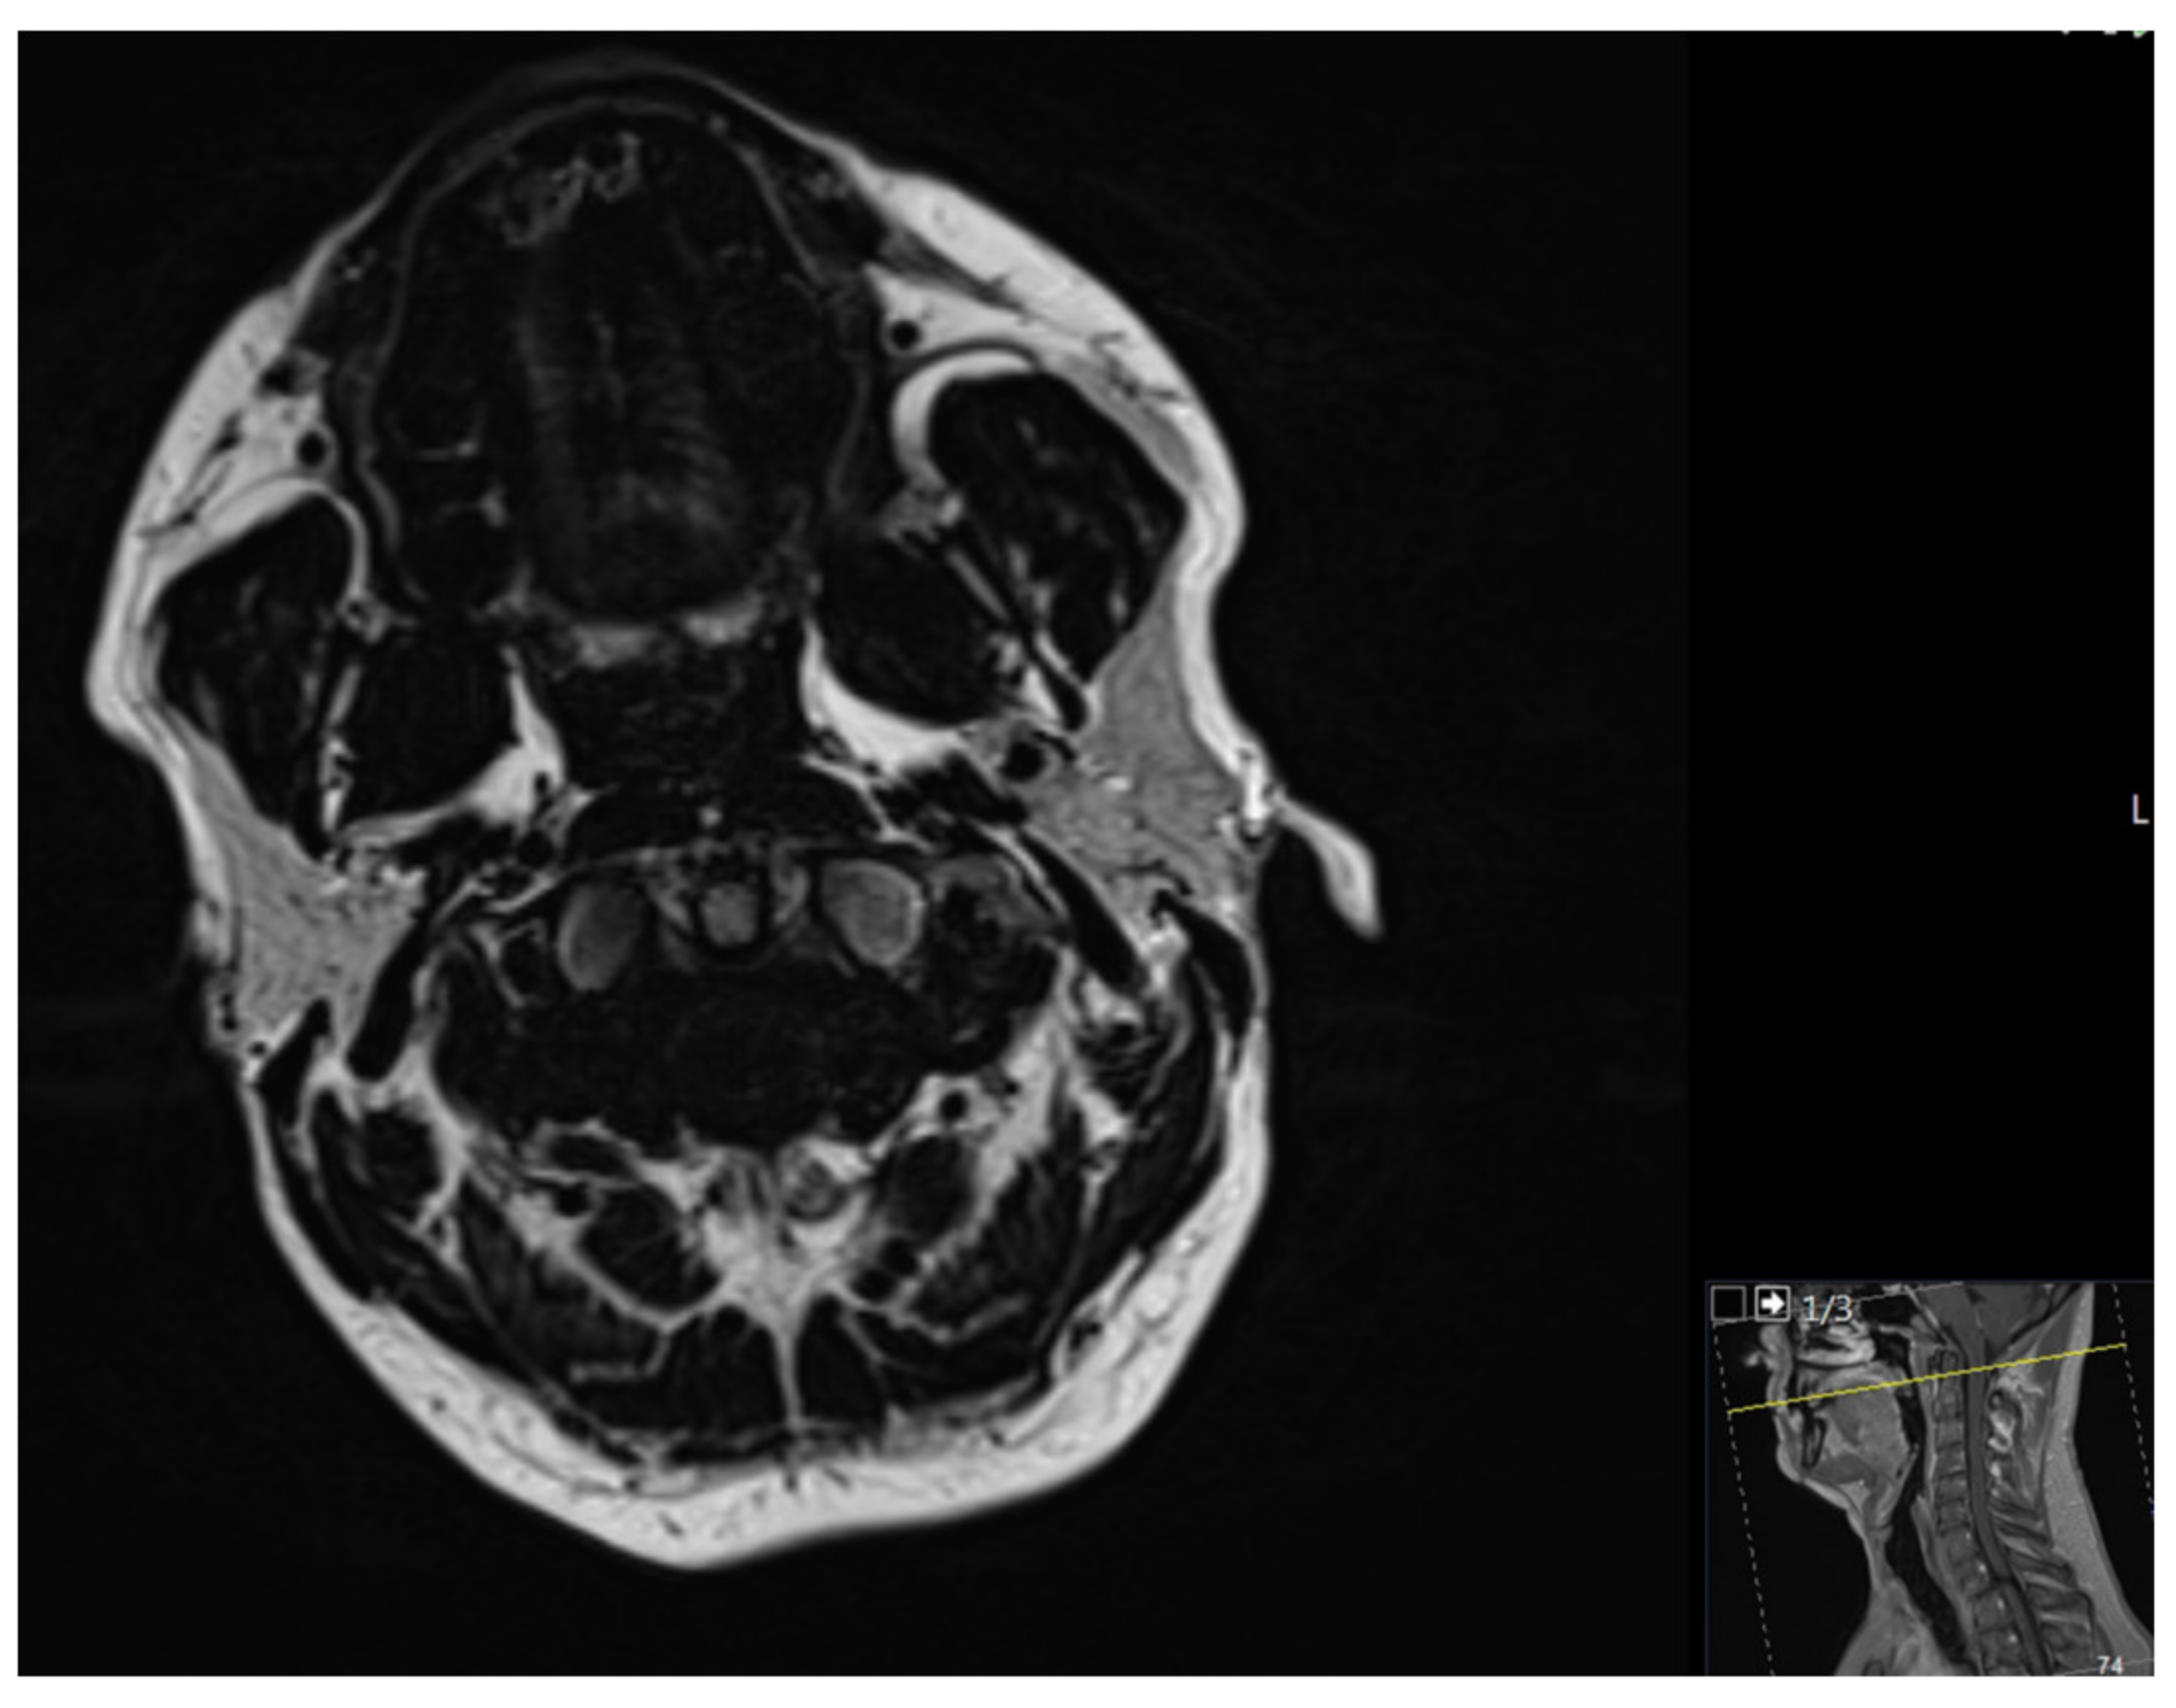

2. Case Report